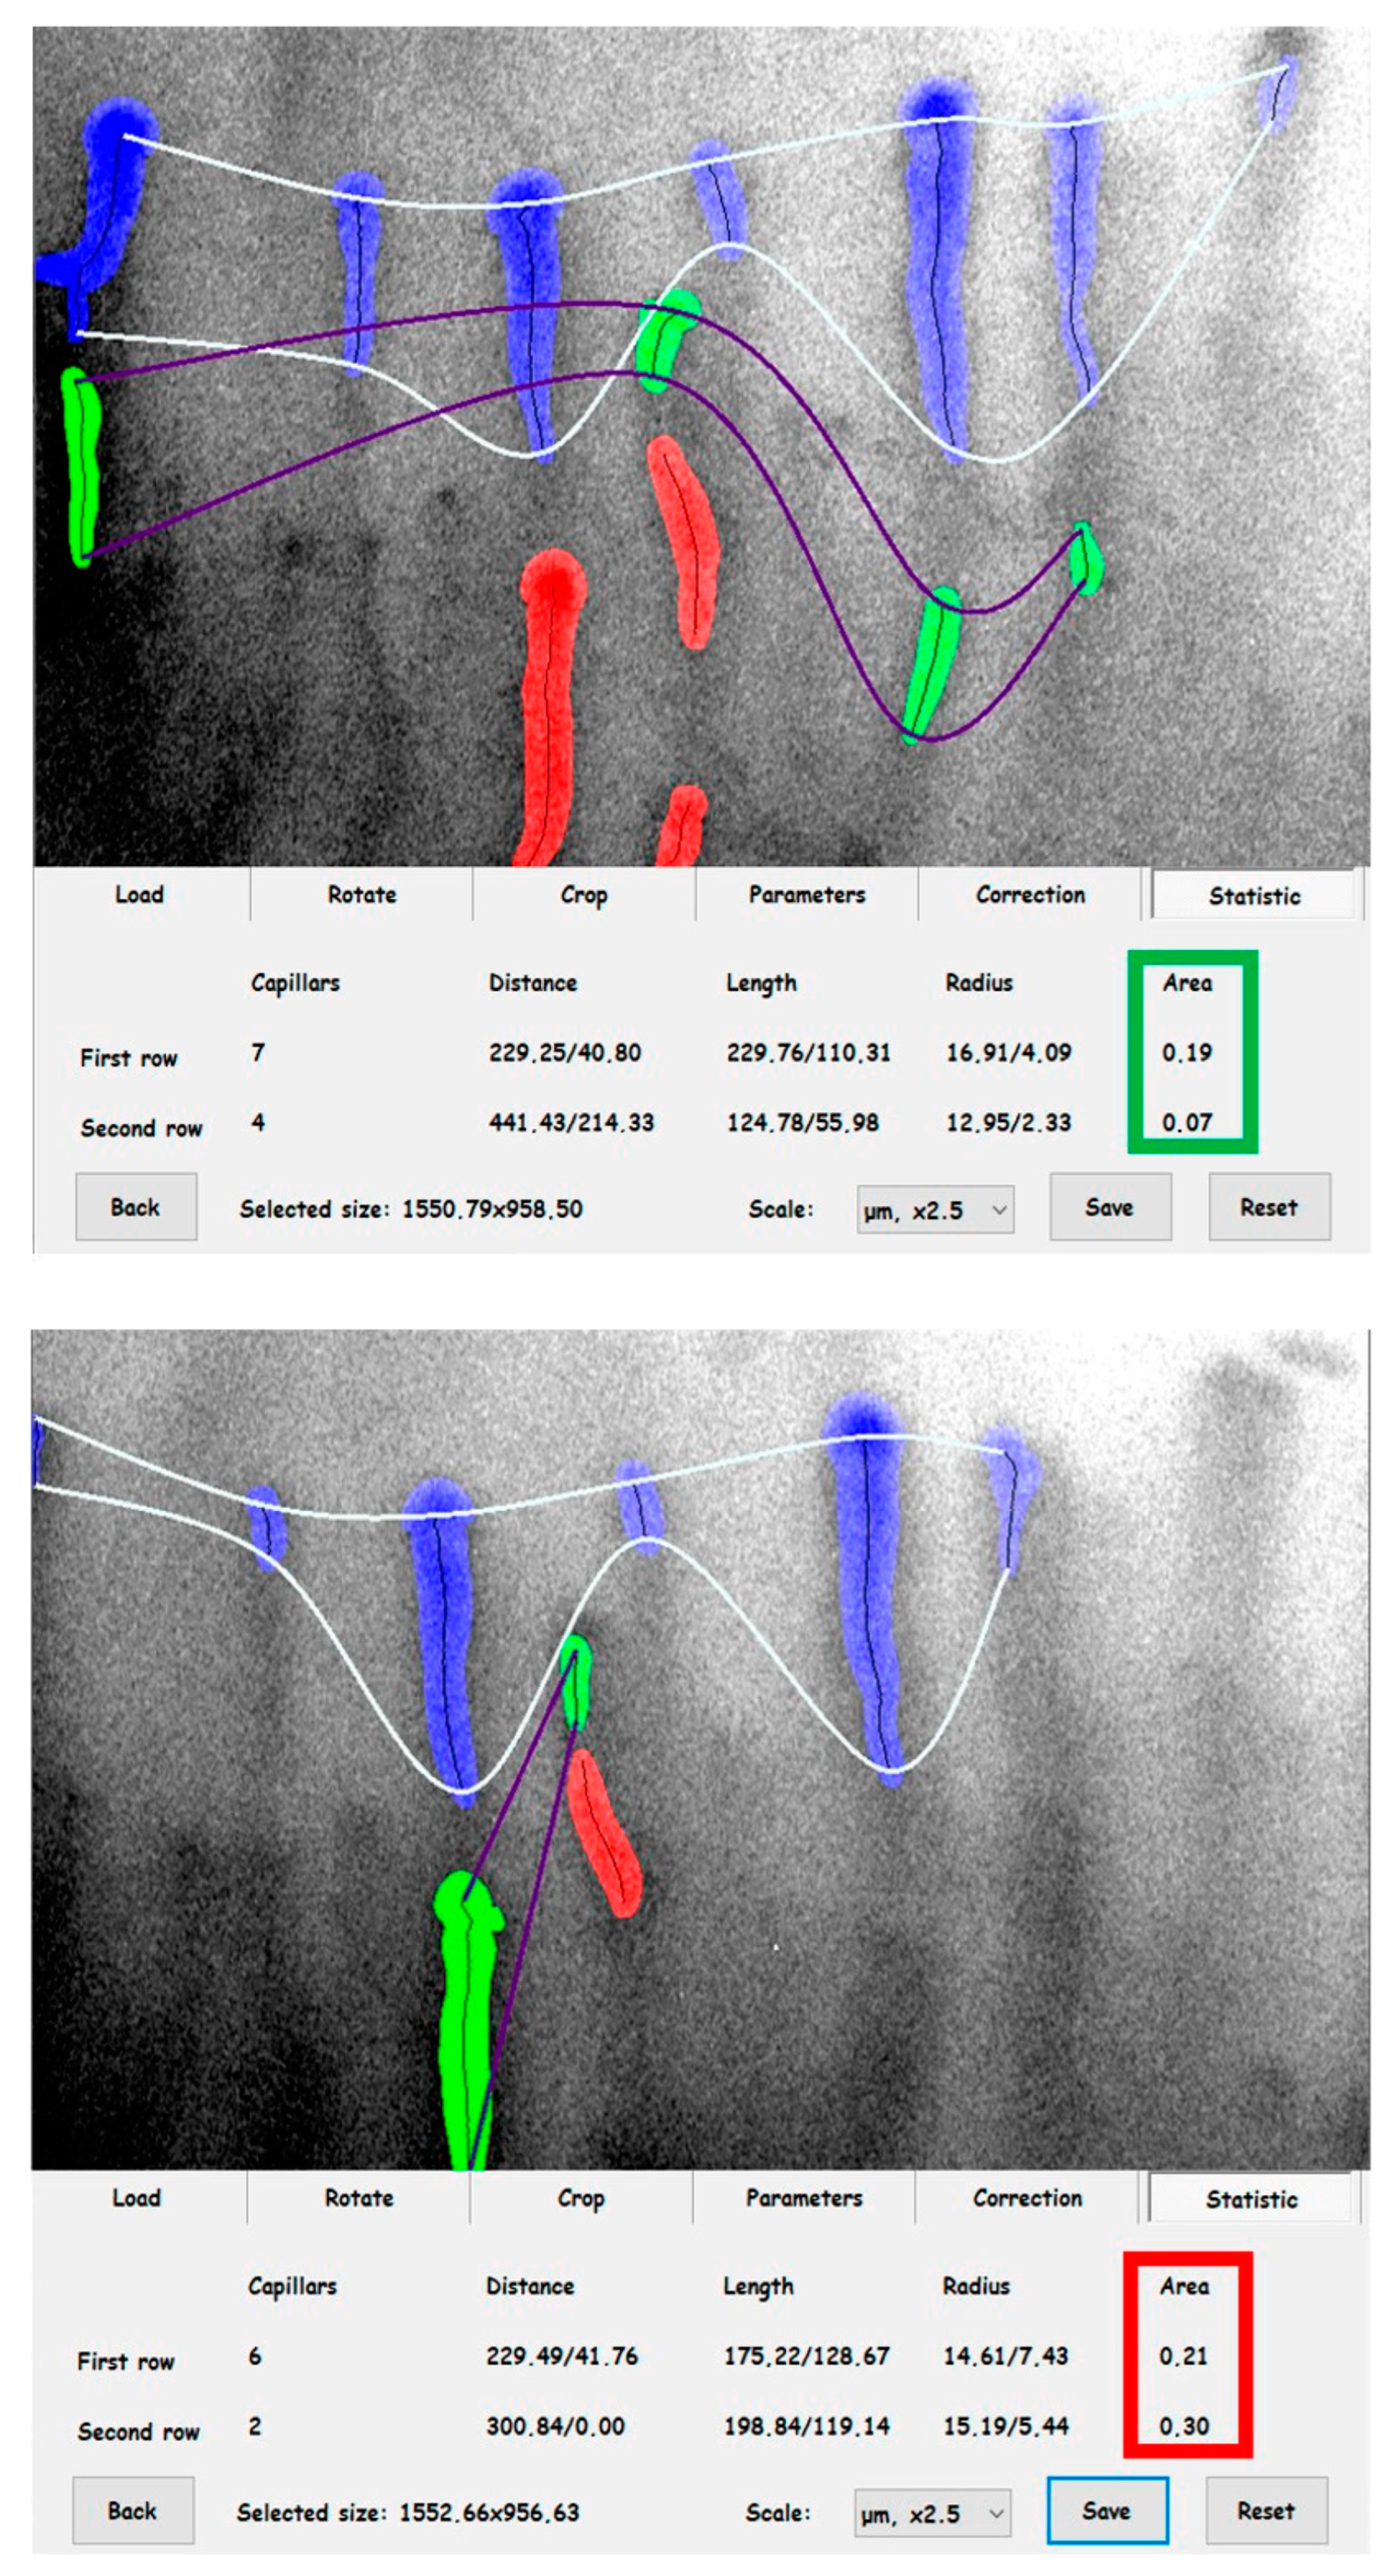

2.2. Evaluation of Cutaneous Microcirculation

- Neubauer-Geryk, J.; Hoffmann, M.; Wielicka, M.; Piec, K.; Kozera, G.; Brzeziński, M.; Bieniaszewski, L. Current methods for the assessment of skin microcirculation: Part 1. Postep. Dermatol. Alergol. 2019, 36, 247–254. [Google Scholar] [CrossRef]